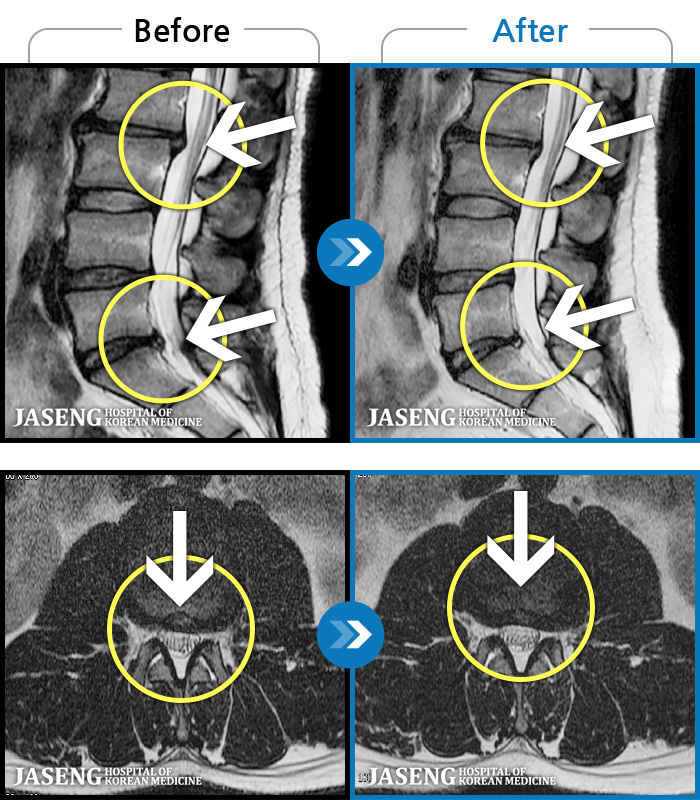

- MRI ġ

MRI ġ

56 MRI ũ ʸ Ȯϼ.

㸮 ϻ .